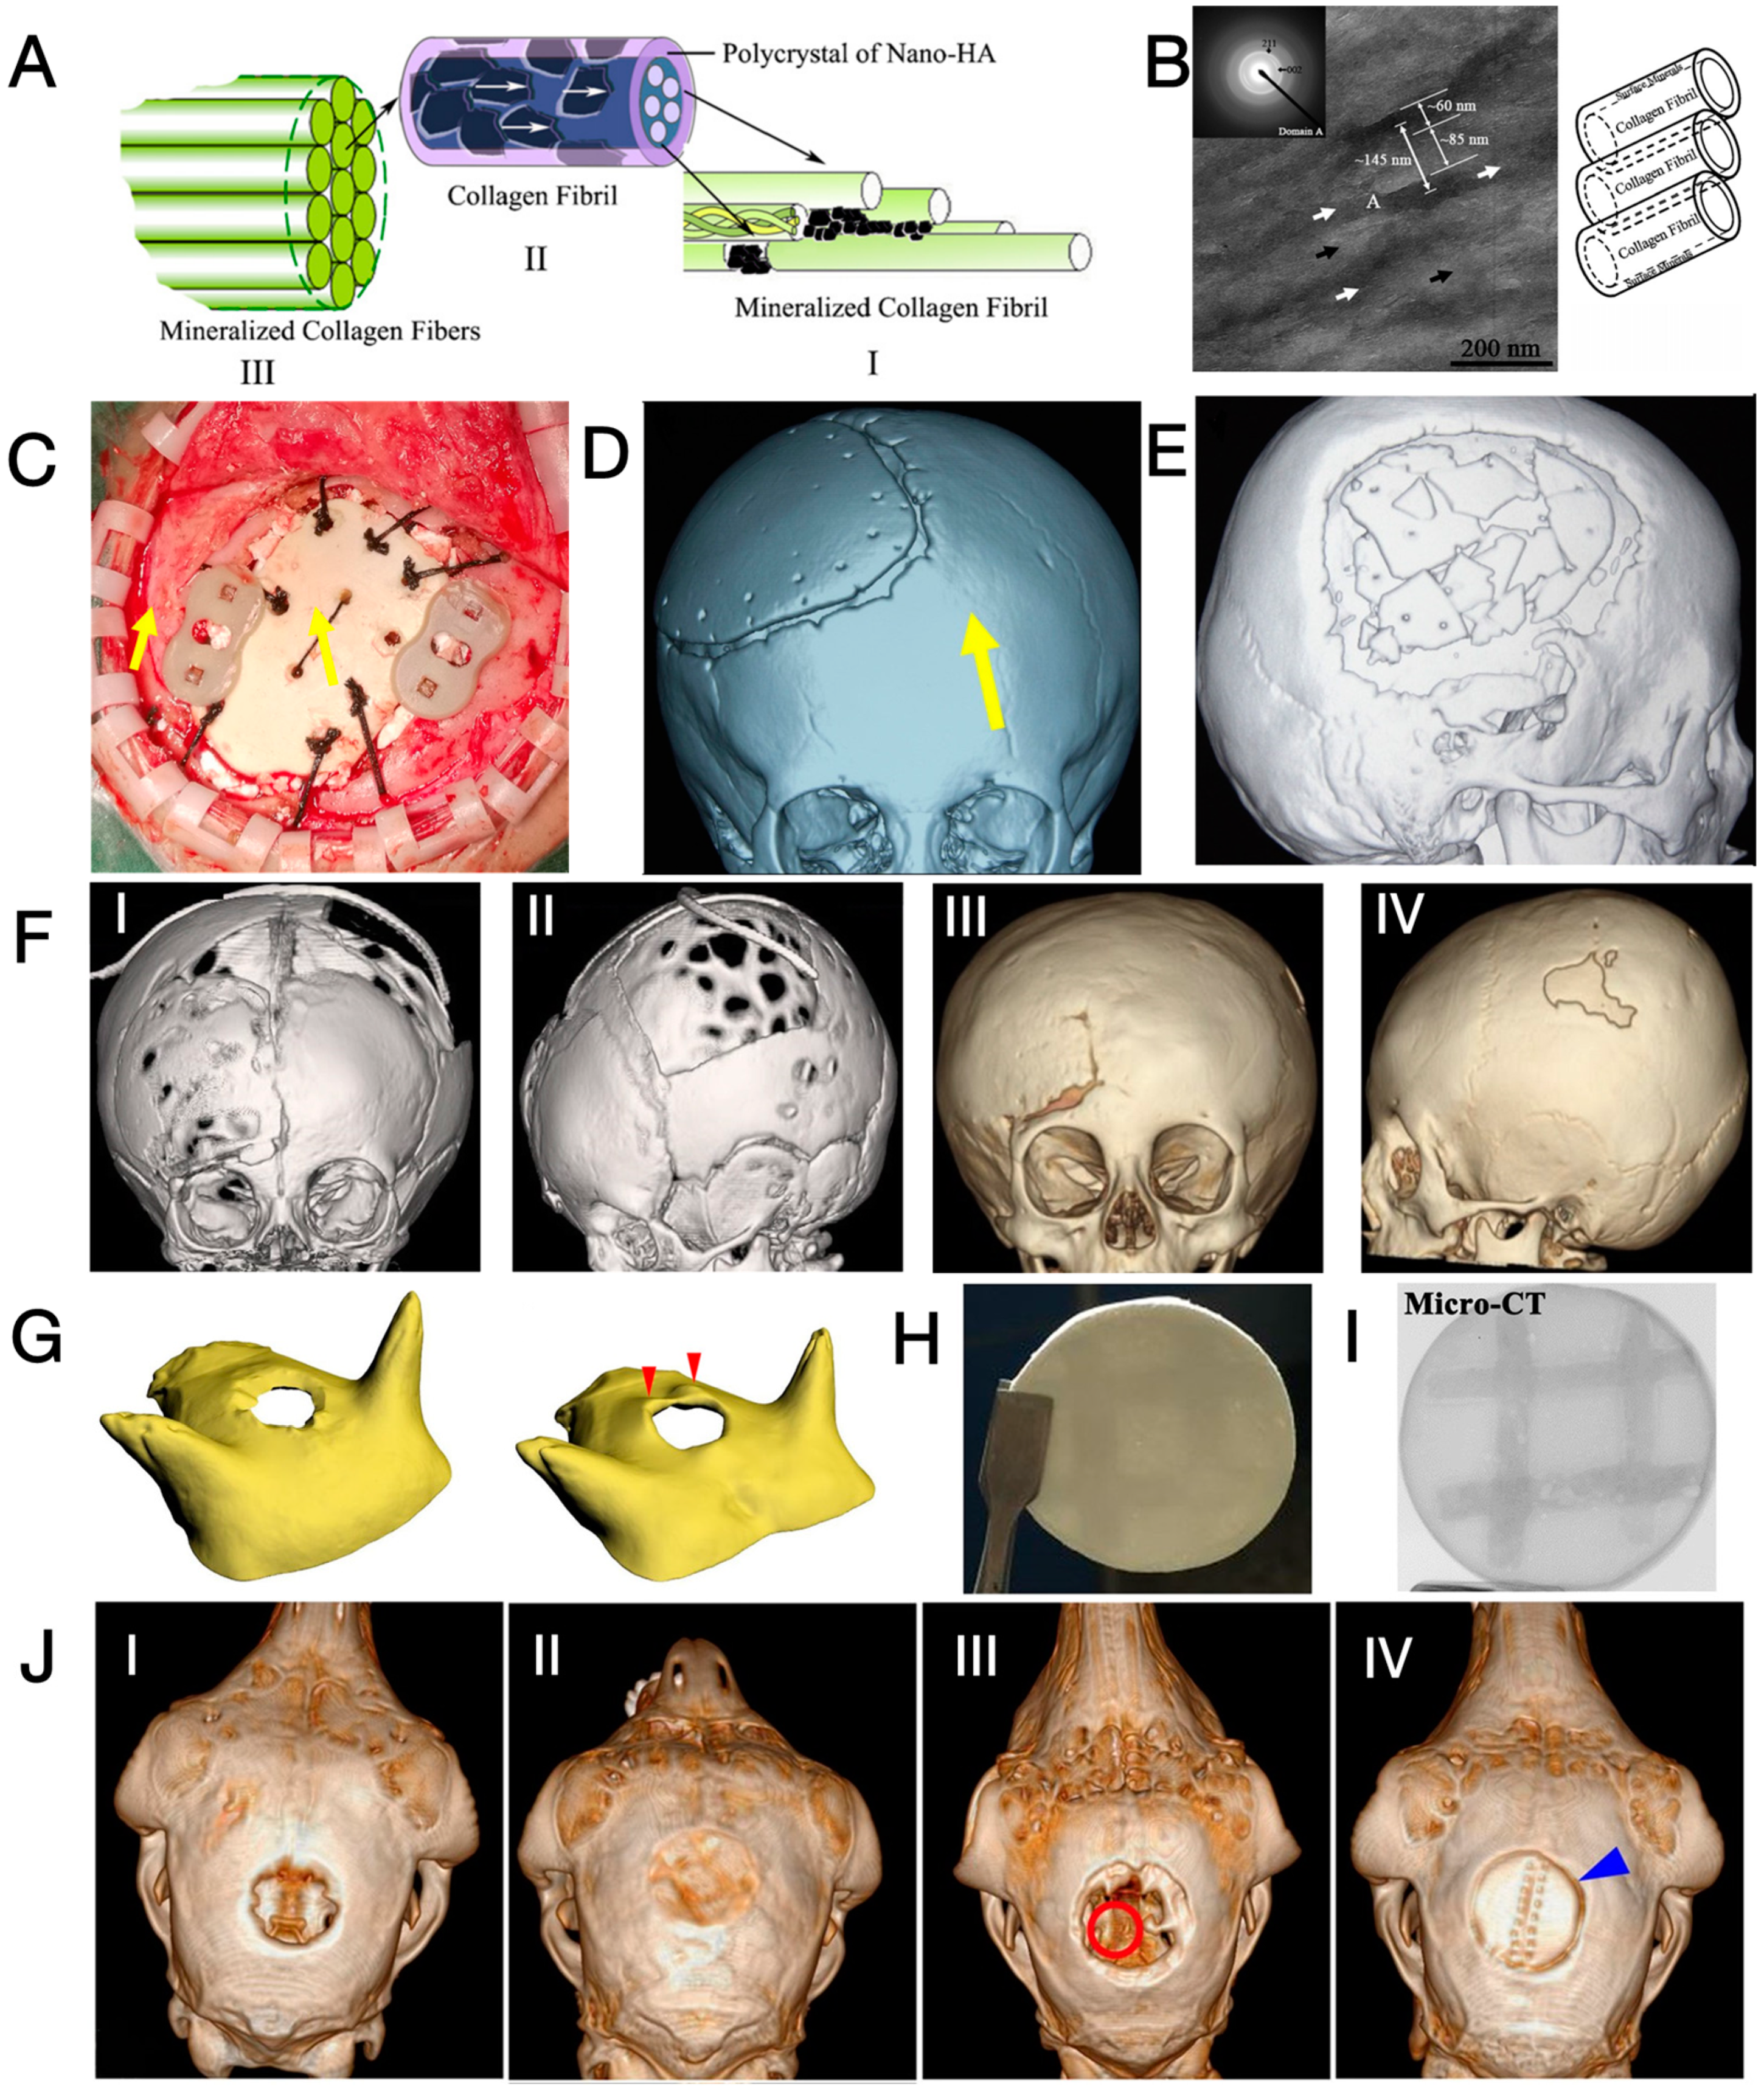

3. Three types of Regenerative Cranioplasty Implants and Progress of Clinical Translation

3.1. CaP/Ti Composites

3.2. Mineralised Collagen

3.3. Three-dimensional-Printed PCL and Its Composites

4. Perspectives on Enhancing the Regenerative Cranioplasty Implants

4.1. Enhancing the Osteogenic Potential on the Scalp Side

4.2. Proper Management of Surrounding Soft Tissue

4.3. Endochondral Ossification as an Alternative Ossification Mode

4.4. Consideration of the Local Mechanical Environment